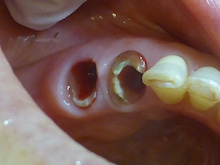

被せものが取れてきた 患者さんです。

虫歯の茶色の部分は

とったあとの写真です。

ここで、虫歯の取り残しないか

齲蝕検知液と呼ばれる薬をかけます。